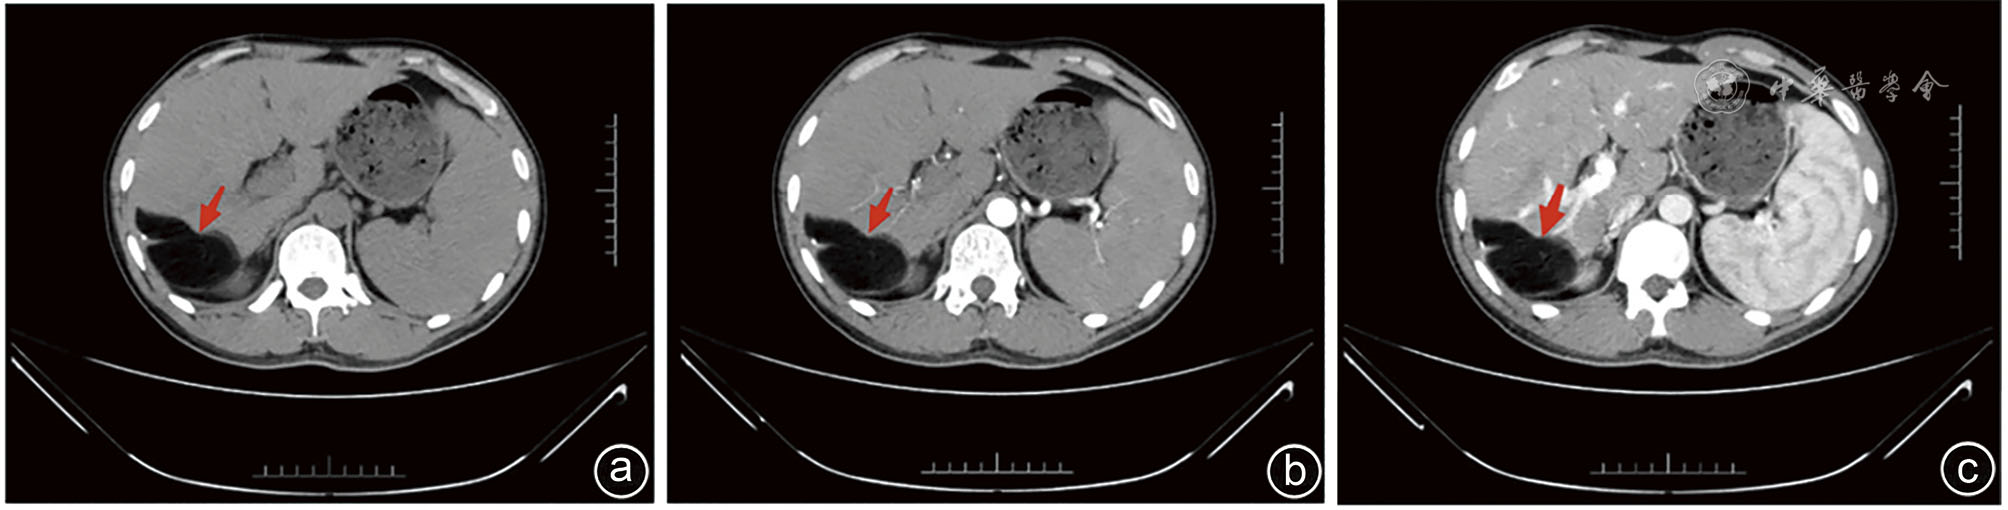

Clinical data of a 32-year-old male patient with hepatic lipoma admitted to Department of Hepatobiliary and Pancreatic Surgery of the Second Affiliated Hospital of Kunming Medical University in November 2023 were retrospectively analyzed. He was hospitalized due to a liver-occupying mass during physical examination. Physical examination revealed nontender abdomen. Complete blood count, blood biochemistry, coagulation function and AFP level was detected normal, while CA50 level was increased. Abdominal ultrasound showed hyperechoic area in the space between liver and kidney. Contrast-enhanced ultrasound revealed that the lesions showed uneven and slight hypoenhancement in the early stage and hypoenhancement in the late stage. Abdominal contrast-enhanced CT showed subcapsular fat density shadow in the right posterior lobe of liver. MRI showed round-like long T1 and long T2 signal shadows in the subcapsular area of the right posterior lobe, without enhancement. Spleen was significantly enlarged. No abnormality was found in parenchymal signals, and no enhancement was observed. MRCP showed no dilatation was seen in the intra-and extra-hepatic bile ducts. Literature review about liver lipoma was conducted and the experience of diagnosis and treatments was summarized.